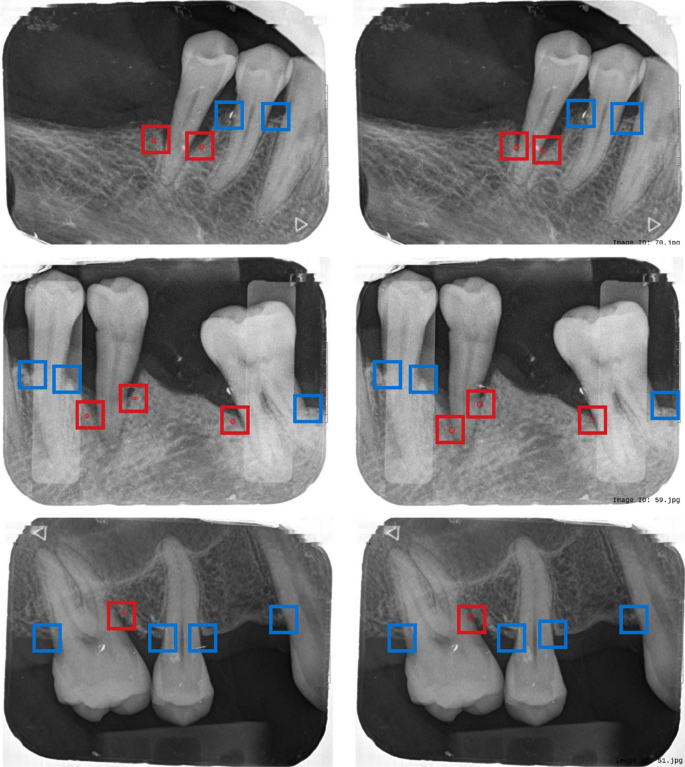

Out of 720 expert-annotated cases, 639 were retained for evaluation after excluding incomplete predictions. On this dataset, the proposed method achieved an accuracy of 0.869, precision of 0.985, recall of 0.826, and sensitivity of 0.872. The confusion matrix is presented in Figs. 11, 12 displays the results after applying the mathematical calculations to the bone level line and tooth boundary results. The left column presents a set of ground truth values for bone loss cases marked by dental professionals, while the right column shows the bone loss cases identified by the proposed methodology. In both columns, red circles indicate angular bone loss, and other markings represent horizontal bone loss.

Comparison of bone loss patterns between ground truth (left) and predicted results (right). Red small circles indicate angular bone loss cases predicted by the system. The red rectangle highlights angular bone loss cases, while the blue rectangle highlights horizontal bone loss cases.